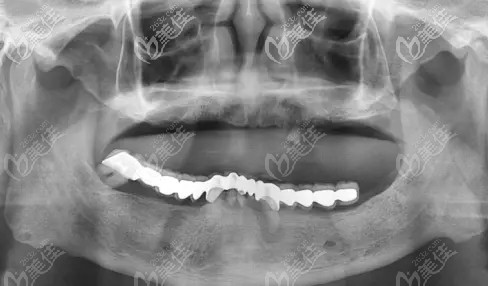

我牙齿一直不好,前段时间去医院检查,医生说我的牙齿已经三度松动了,建议还是做全口种植牙,但是我还是犹豫了,因为自己的牙齿还没有脱落不想拔牙。不过这段时间发现牙齿已经基本不能咬东西了,思来想去还是得做种植牙,然后就在网看好多人说韩国登腾allon4全口种植牙效果不错,性价比也高,不知道5万元能不能做?

牙齿三度松动表示松动幅度在2毫米以上,基本上是已经不能咀嚼了,如果医生诊断的没有错的话,那确实需要做全口种植牙。

首先要了解一下其实全口种植并不是每一个颗牙齿都要种植,差不多种植牙10颗左右,像你说的韩国登腾allon4全口种植牙的价格也基本上是需要10万左右的,5万是做不了的,所以千万不要被低价吸引了,还是要慎重一点,毕竟效果才是更重要的。

就像你说的登腾allon4全口种植牙效果是不错的,价格相对来说也便宜一些,但是你说的5万做个半口还差不多,全口的话是肯定不行的,所以你还是要有心理准备才行。

你好,我爸爸的年龄和你差不多,也是做得登腾allon4半口种植牙差不多是花了6万多,所以我觉得你的情况想要做全口5万肯定是不够,我感觉怎么着也得10万多吧,你还是多咨询看看,不过太便宜的还是不要做,效果感觉没什么保障。